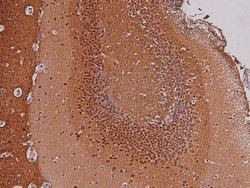

Phospho-p27 Kip1 (Thr157) Polyclonal Antibody for Western Blot, ICC/IF, IHC (P)

| Immunohistochemistry (Paraffin), Western Blot, Immunocytochemistry | |

| A synthesized peptide derived from human CDKN1B(Accession P46527), corresponding to amino acid residues around phosphorylated Thr157. | |